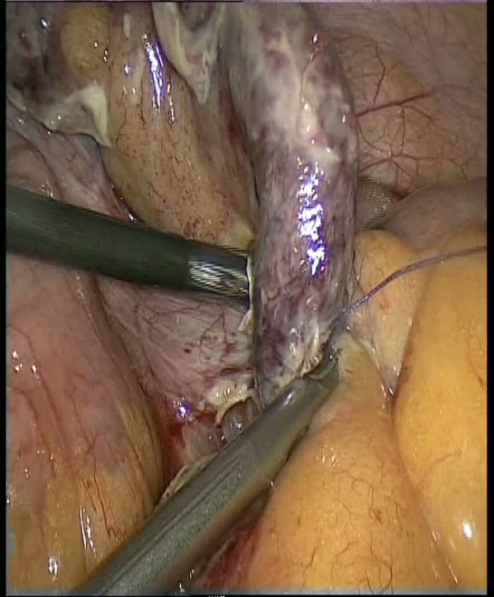

Kəskin appendisitin standart müalicəsi açıq və ya laparoskopik appendektomiyadır. Bu prinsipdən nadir istisnalar var: infiltrativ appendisit, əməliyyat riski çox yüksək olan xəstələrdə ağırlaşmamış appendisit əlamətləri. Son illər ağırlaşmamış appendisitlərdə antibiotikoterapiyanın faydalı olduğu barədə məlumatlar var.

- Laparokopik appendektomiya ən çox tövsiyə olunan üsuldur, həm ağırlaşmamış, həm ağırlaşmış appendisitlərdə, hətta hamilələrdə aparıla bilər. Qadınlarda və diaqnostik çətinlikdə laparoskopiya ilk seçim sayılır.

- Açıq appendektomiya ədətən sağ aşağı çəp (McBurney nöqtəsindən keçən kəsik) və ya sağ aşağı pararektal kəsiklə icra olunur.

- Əməliyyat vaxtı normal görünən appendiksi çıxarmaq və patoloji müayinəyə göndərmək lazımdır (5-20% hallarda appendisit makroskopik görünməyə bilir), lakin qarın boşluğunu diqqətli təftiş etmək də unudulmamalıdır.

- Antibiotikoterapiya əməliyyatlardan sonrakı ağırlaşmaların profilaktikası üçün aparılır, əməliyyatdan əvvəl bütün xəstələrə, sonra isə yalnız perforativ appendisitlərdə tövsiyə edilir.